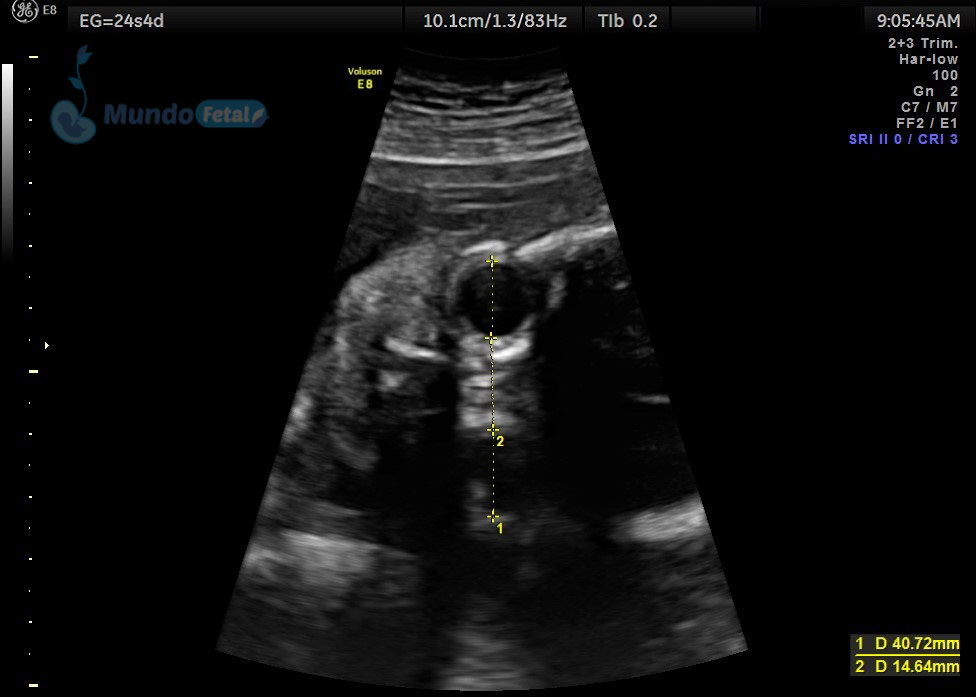

LONGITUD-CERVICAL1

Entre las 18 y 22 semanas, el feto ha desarrollado la mayoría de sus estructuras anatómicas, permitiéndonos valorar de manera detallada todos los órganos del bebe, descartando anomalías anatómicas fetales y datos de cromosomopatías. Prediciendo además preeclampsia (Doppler de arterias uterinas) y parto prematuro (por medio de la medición de la longitud del cérvix). En manos expertas, la detección de anomalías anatómicas supera el 80%.